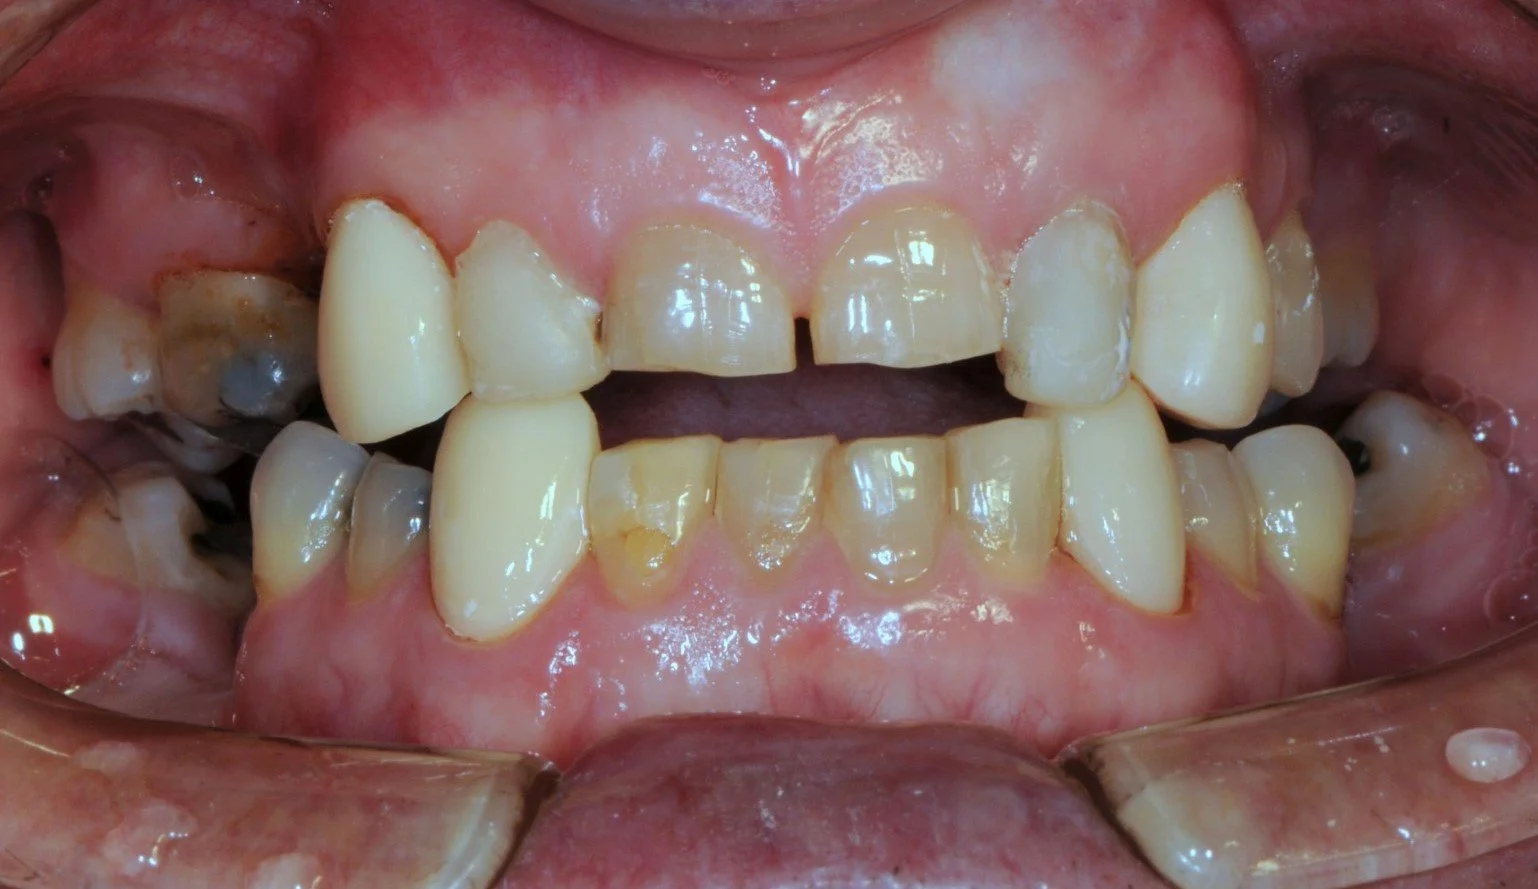

This 65 year old patient had numerous dental problems including decay, periodontal gum disease involving moderate to concerning future bone loss, missing teeth, heavily filled teeth and an extremely difficult very deep overbite.

-

An OPG radiograph illustrating a variety of dental concerns and the presence of 2 implants in the lower jaw in the first premolar regions, namely, 34 and 44.

Part of the deep overbite and a heavily discoloured top left number 2 lateral incisor previously extracted, root sectioned and amalgam filled prior to reattaching as a bonded bridge tooth to the adjacent top left number 3 canine tooth.

The remaining lower 6 front teeth that were deemed to have insufficient bone for longevity and unsuitable for a bite reconstruction, these teeth were extracted.